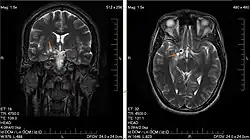

| Glioma in the left parietal lobe (brain CT scan), WHO grade 2 | |